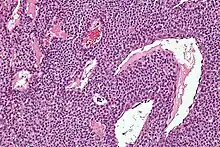

Micrograph of a glomus tumor. H&E stain. | |

Histologically, glomus tumors are made up of an afferent arteriole, anastomotic vessel, and collecting venule. Glomus tumors are modified smooth muscle cells that control the thermoregulatory function of dermal glomus bodies. As stated above, these lesions should not be confused with paragangliomas, which were formerly also called glomus tumors in now-antiquated clinical usage. Glomus tumors do not arise from glomus cells, but paragangliomas do.

By histopathology, glomus tumors can be termed as follows:[7]

- Solid glomus tumor (75% of cases): Consisting predominantly of glomus cells, with poor vasculature and rare smooth muscle cells.

- Glomangioma (20% of cases): Tumors with a prominent vascular component.

- Glomangiomyoma (5% of cases): Tumors with prominent vascular and smooth muscle components.